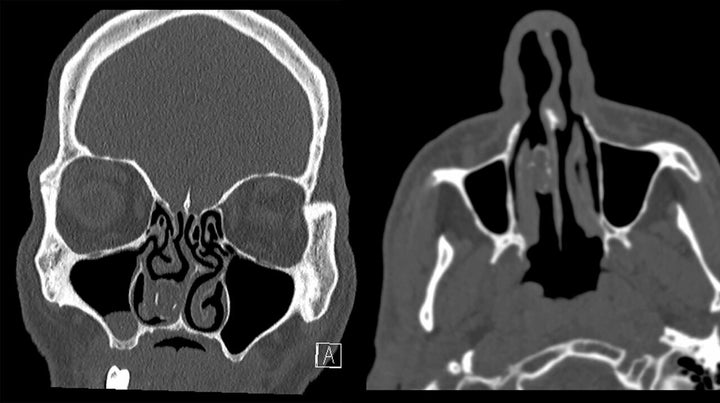

According to a study published earlier this week in BMJ Case Reports, appropriately titled “Nose out of Joint,” a CT scan showed what looked like a calcified lesion in the nasal passage.

Yeah, yeah, pictures or it didn’t happen. Here you go: